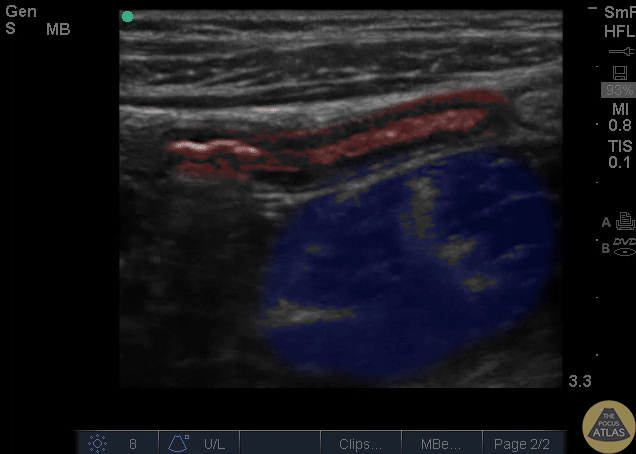

Colorized Appendicitis Images - Colorized Appendix and Psoas

Red = Appendic Blue = Psoas Images provided by Sathya Subramaniam - Children’s Hospital of Philadelphia, edited by Matthew Riscinti - Kings County Emergency Medicine